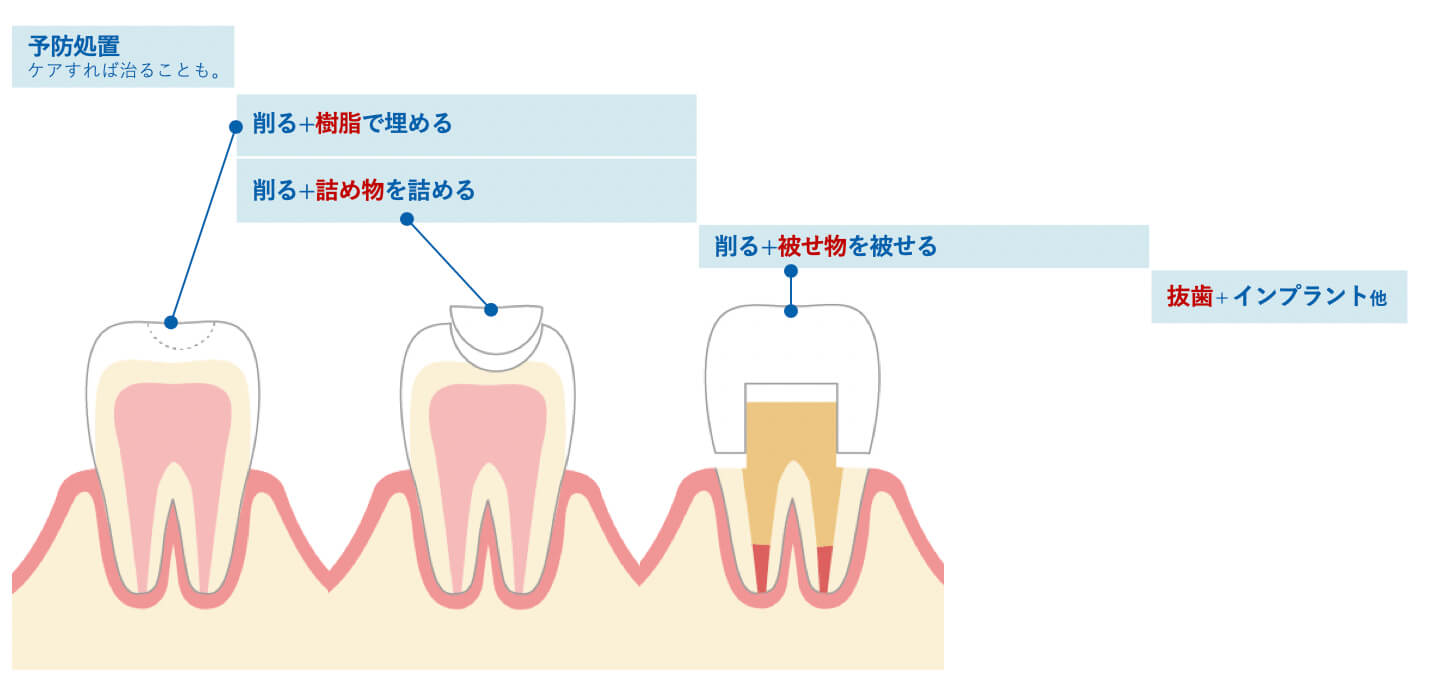

虫歯の治療について

虫歯の治療は、歯を削って塞ぐことが基本になります。

虫歯治療の流れ

①虫歯があります

②虫歯部分を染色

小さく見えても、中で大きく広がっていることもあります。

③削ります

④一見、虫歯がないように見えますが…

⑤詰め物を外すと、虫歯になっていることもあります(二次虫歯)

内面が黒ずんでいるのは、カビや銀歯の錆びが、飲み込まれずに溜まっているからです。

⑥更に歯を削ることになります

削った部分を補うパーツは、素材選びが重要になります。